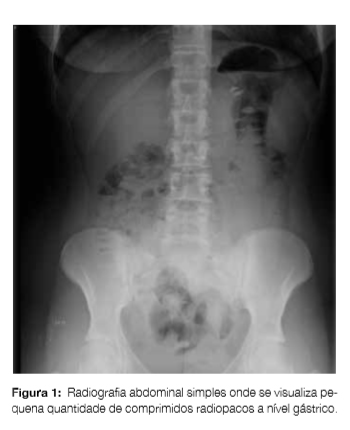

Apresenta-se o caso de uma jovem de 18 anos, caucasiana, com anemia ferropénica, suplementada com sulfato ferroso. Foi admitida no Serviço de Urgência 5 horas após intoxicação voluntária com 13 comprimidos de desogestrel + etinilestradiol 150 + 20 mcg e 25 de sulfato ferroso 329,7 mg de libertação prolongada (doseamento ferro elementar: 37,5 mg/kg). Após a ingestão iniciou cefaleias, dor abdominal difusa, náuseas e teve vómito com saída de inúmeros comprimidos. Encontrava-se apirética, com tensão arterial de 120/79 mmHg, frequência cardíaca 112 batimentos/minuto, saturação de oxigénio em ar ambiente de 99%, glicemia capilar 125 mg/dL, corada e hidratada, auscultação cardiopulmonar sem alterações, abdómen indolor e sem rash cutâneo. Foi monitorizada, iniciou analgesia e fluidoterapia. O estudo analítico realizado às 8 horas após a ingestão revelou: hemoglobina 12,8 g/dL, VGM 90,0fL, HGM 29,4 pg, sem leucocitose ou neutrofilia e plaquetas 177 x 109/L, estudo de coagulação, função renal e provas hepáticas sem alterações. Ferro sérico 537 ug/dL, transferrina 409 mg/dL, saturação transferrina 131,3%, ferritina 13 ng/mL. Exame sumário e pesquisa de drogas de abuso na urina sem alterações. Gasimetricamente: pH 7,414, pO2 101,8 mmHg, pCO2 35,2 mmHg, HCO3- 22 mmol/L, lactatos 0,3 mmol/L, anion gap 7,60 mmol/L. Na radiografia abdominal verificava-se presença de pequena quantidade de comprimidos radiopacos na câmara gástrica (Fig 1). Foi contactado o Centro de Intoxicações e, após conhecimento e discussão conjunta do caso, não realizou lavagem gástrica e iniciou terapêutica quelante de ferro com desferroxamina 15 mg/kg/h (12 horas após ingestão), mantendo monitorização. Objetivou-se diminuição gradual dos valores de ferro sérico, sendo suspensa a perfusão 26 horas após a ingestão. Manteve vigilância até às 40 horas, encontrando-se assintomática, com o valor de ferro sérico normal (Tabela 1). Foi avaliada por Psiquiatria, tendo alta.

Na admissão não foi realizada lavagem gástrica. Não está recomendada por rotina, sendo muitas vezes ineficaz a remover os comprimidos de ferro do estômago.7 Deve ser ponderada quando a radiografia abdominal mostra elevado número de comprimidos a nível gástrico, devendo ser repetida a radiografia após o procedimento para avaliar a sua eficácia.4,6 Neste caso, considerou-se sem benefício pela estabilidade clínica, pelo episódio de vómito e por apresentar pequena quantidade de comprimidos a nível gástrico, ponderando os possíveis riscos (progressão distal dos comprimidos, perfuração de víscera ou aspiração de vómito).7